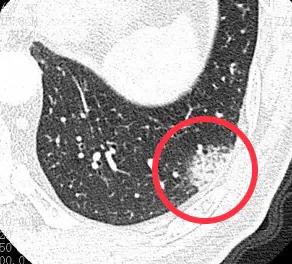

1.一过性磨玻璃结节

一过性磨玻璃结节就是指一开始肺部ct发现有磨玻璃结节,但是经过消炎吃药之后,磨玻璃结节消失了。相信很多朋友都有这种经历。这种磨玻璃结节,称之为一过性磨玻璃结节,都是细菌感染引起的。通过治疗之后都是可以完全治愈的。